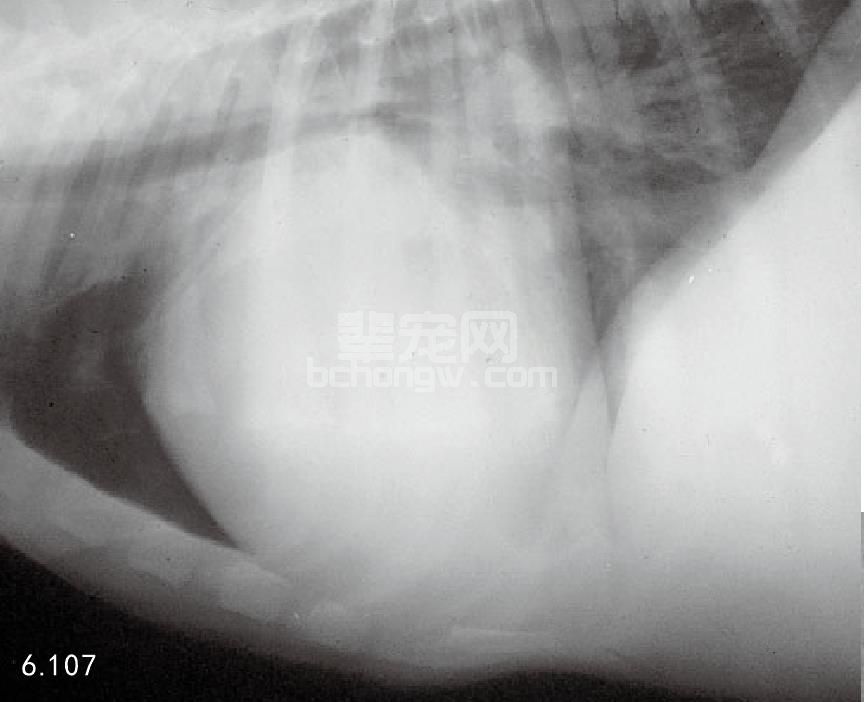

图6.107 患二尖瓣发育异常的18周龄大丹犬的胸部侧位片。